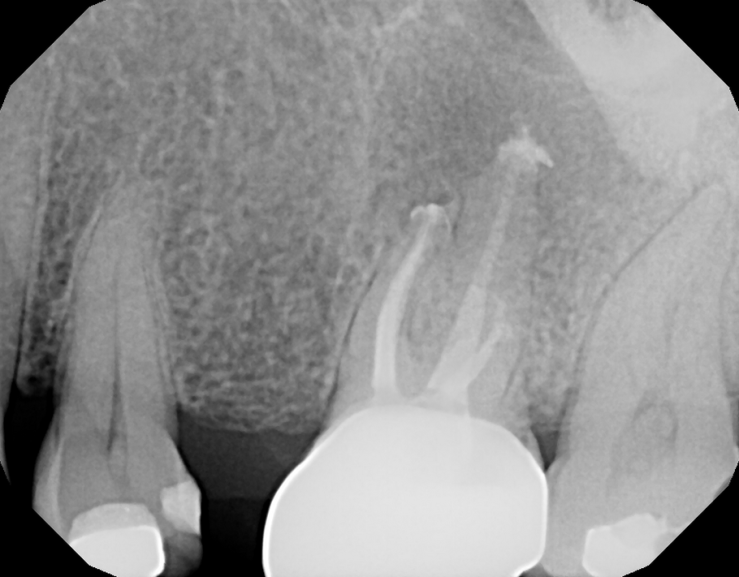

#14 MB root amp with GTR